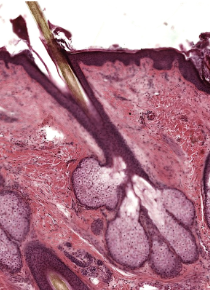

Hair + 3 types

composed of dead, keratinized epidermal cells

have sensory mechanisms

Hair structures

shaft - above skin surface

follicle - below level of skin

root - penetrates into dermis

epithelial root sheath

dermal root sheath

arrector pili muslce

Sebaceous (oil) glands

connected to hair follicles

look like popcorn bubble